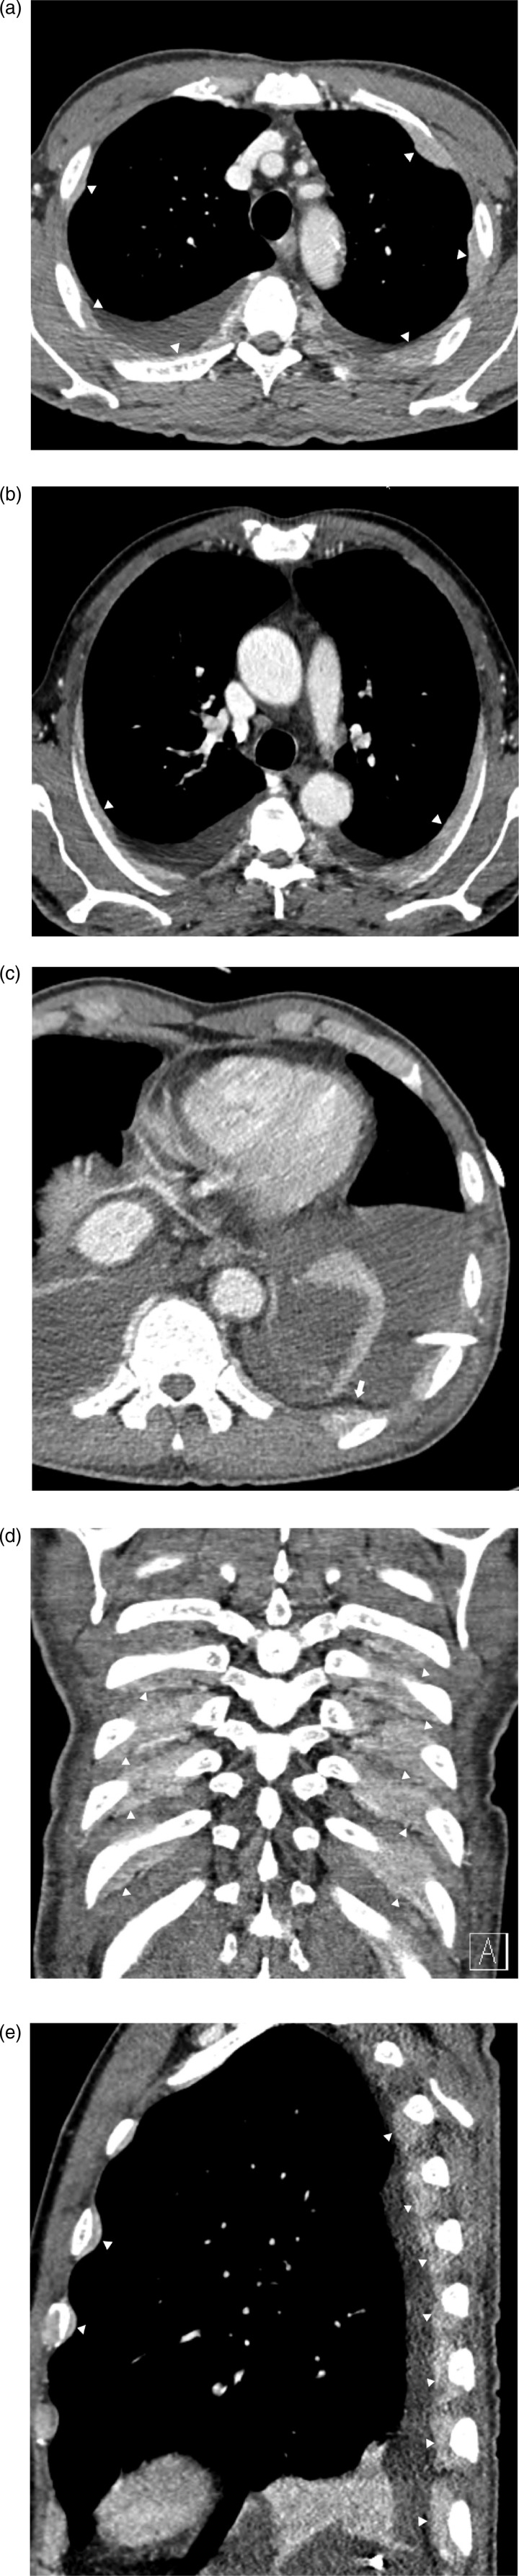

Extramedullary involvement of multiple myeloma is an uncommon and aggressive condition characterized by proliferation of monoclonal plasma cells located outside the bone marrow. This report describes the imaging findings of a patient who presented with continuous soft-tissue disease on the ribs, suspected as extrapleural space tumors on chest CT. The patient was diagnosed with multiple myeloma through surgical biopsy of the tumor and bone marrow.